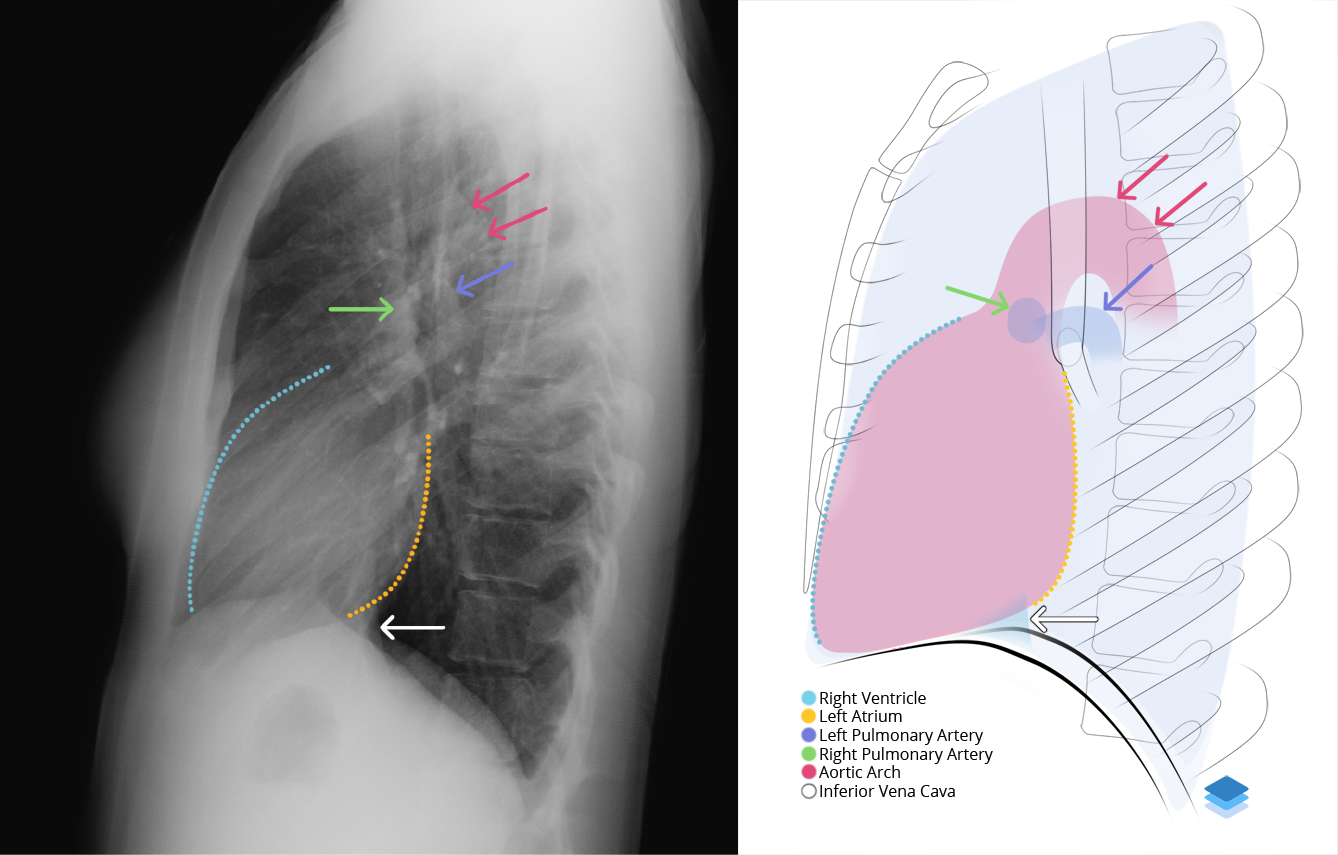

Chest radiograph & CT anatomy